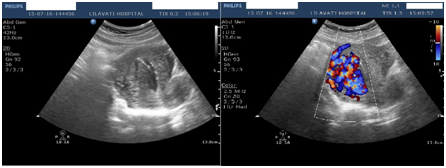

Histopathology of the tissue revealed degenerated and necrosed bits of decidua and few degenerate chorionic villi admixed with fibrin and blood s/o retained and degenerate products of conception (No features of Placental site trophoblastic tumor). After 6 weeks, patient was followed up & it was found out that per vaginal bleeding had diminished gradually over the period of 4 weeks & stopped completely thereafter. The pelvic ultrasound with Color Doppler confirmed diminished size of AVM with diminished vascularity (Figure 4).